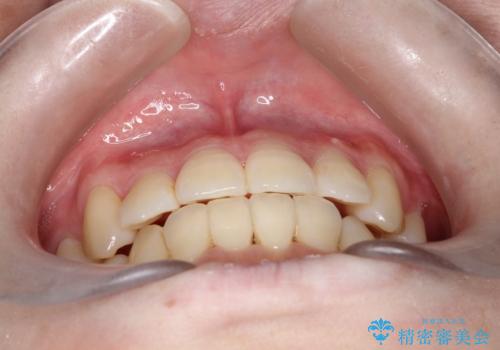

治療に関して期間こそかかってしまったものの、見た目、嚙み合わせ及び、治療期間や施術内容に大変ご満足いただきました。

コンプレックスだった前歯のガタガタがここまで綺麗になるなんて!!